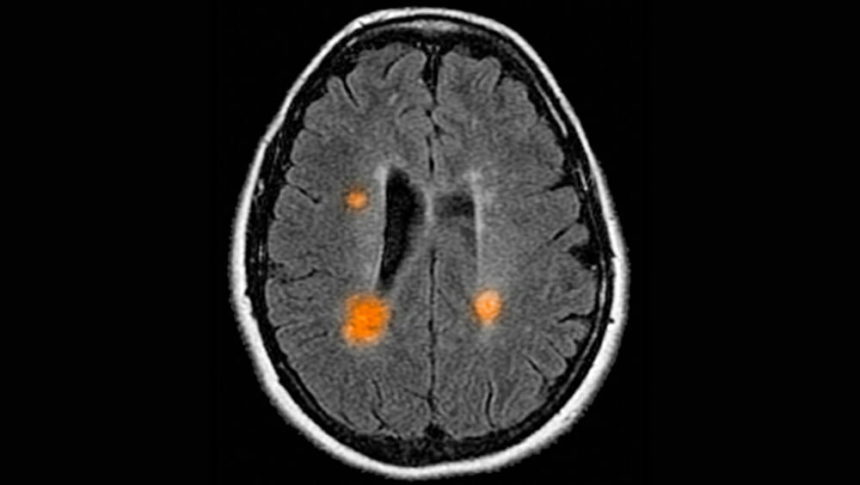

Roztroušená skleróza je u každého jiná, a to jak s ohledem na vývoj, tak projevy, i proto se jí často přezdívá nemoc mnoha tváří. Projevy této diagnózy se totiž liší člověk od člověka dle toho, na jakém místě v mozku a míše dojde k poškození neuronů.

Kvůli tomuto narušení nemohou být správně přenášeny signály mezi mozkem a zbytkem těla, což zaznamenáme právě různými projevy. U někoho jde o potíže se zrakem, únavou nebo třeba koordinací pohybů.